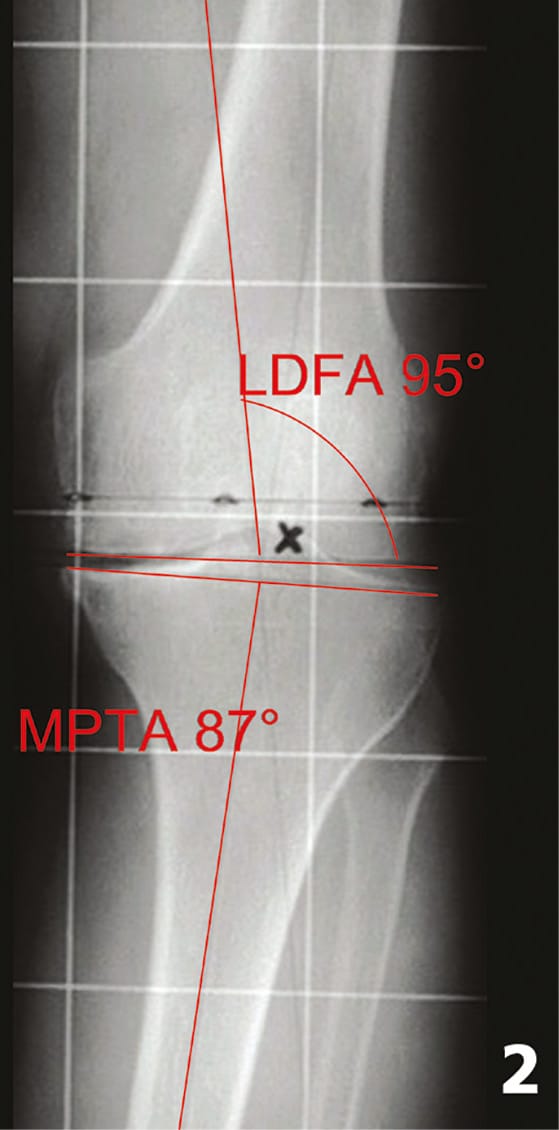

The planning in the frontal plane was performed on the full leg x-ray and included deformity analysis according to Paley [21] Paley D, Herzenberg JE, Tetsworth K, McKie J, Bhave A (1994). Deformity planning for frontal and sagittal plane corrective osteotomies. Orthop Clin N Am 25: 425-465. The mechanical axis of femur, tibia and baselines of distal femur and proximal tibia are drawn on the radiograph (Figure 1 and 2). The varus or valgus malalignment, the mechanical distal lateral femur angle (LDFA - normal 88°, range 85-90) and mechanical medial proximal tibia angle (MPTA - normal 87°, range 85-90) were calculated (Figure 2). Furthermore the individual IM-angle between the mechanical and the anatomical axis of the femur was analyzed. With these four numbers the severity and location of the frontal bony deformity as well as the individual IM-angle could be identified before surgery. Depending on the necessary correction cuts for neutral alignment (LDFA and MPTA 90°), the need for additional soft tissue releases could be estimated also. In the case of figure 1 for example with a contract varus deformity of 12° the valgus correction cuts of 5 mm each on the femur and tibia (1° ~ 1mm) will end up with an further 10 mm increase in the trapezoidal extension gap. Together with the already contract medial soft tissue structures this will need extensive medial releases to correct this contract varus deformity.

Planning is a crucial part of a successful TKA and should include history, clinical examinations, radiographic analysis and planning on a weight bearing full leg length radiograph [22] Pietsch M, Hofmann S (2006). Value of radiographic examination of the knee joint for the orthopedic surgeon (German). Radiologe 46: 55-64. The standardized weight bearing full leg radiograph represent the key for deformity analyzes and planning of the long axis in the frontal plane (Figures 1 and 2). On short x-rays the tibiofemoral angle can be measured only, which does not allow analysis of the deformity and the mechanical axis of the whole leg. The overall mechanical axis, deformity analysis and IM-correction angle are necessary for proper frontal alignment correction [16], Hofmann S, Djahani O, Pietsch M (2007). Conventional navigation without computer and the lateral minimally invasive approach for contract valgus knee (German). Orthopäde 36: 1135-1142[22] Pietsch M, Hofmann S (2006). Value of radiographic examination of the knee joint for the orthopedic surgeon (German). Radiologe 46: 55-64.

With deformity analysis according to Paley [21] Paley D, Herzenberg JE, Tetsworth K, McKie J, Bhave A (1994). Deformity planning for frontal and sagittal plane corrective osteotomies. Orthop Clin N Am 25: 425-465 about half of the varus knees (48%) the bony deformity was located at the femur and the tibia was normal in this study (Figure 1). This means, that the lateral and not the medial condyle was the most distal part for the cutting block positioning at the femur. Additional in valgus knees 35% showed the deformity at the tibia only and in 47% it was located at tibia and femur. As we operate in almost all cases knees with deformities, the frontal distal femur and proximal tibia cuts are individual, depending on the location of deformity only and should be planned by deformity analyzes using LDFA and MPTA (see Table 2).